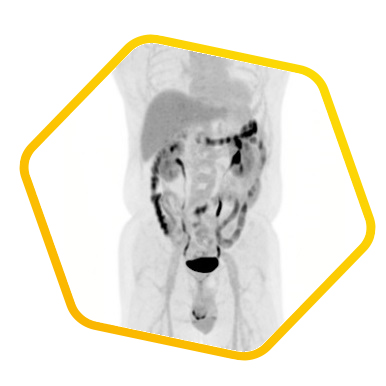

脑神经内分泌肿瘤

双示踪剂PET/CT (F-18 FDG及Ga-68 DOTATATE) 用於评估脑神经内分泌肿瘤体内的扩散情况

![]() [F-18] FDG |

![]() [Ga-68] DOTATATE |